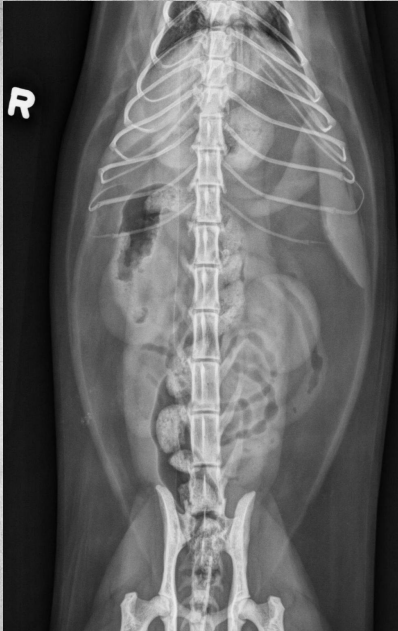

●9 yo female sterilized German

Shepherd

●Anorexia, lethargy

●Weakness

● Mass effect, bowels lifted dorsally

and caudally

● Round shadow cranially to tail of

the spleen

● Splenomegaly, splenic mass. hemangiosarcoma